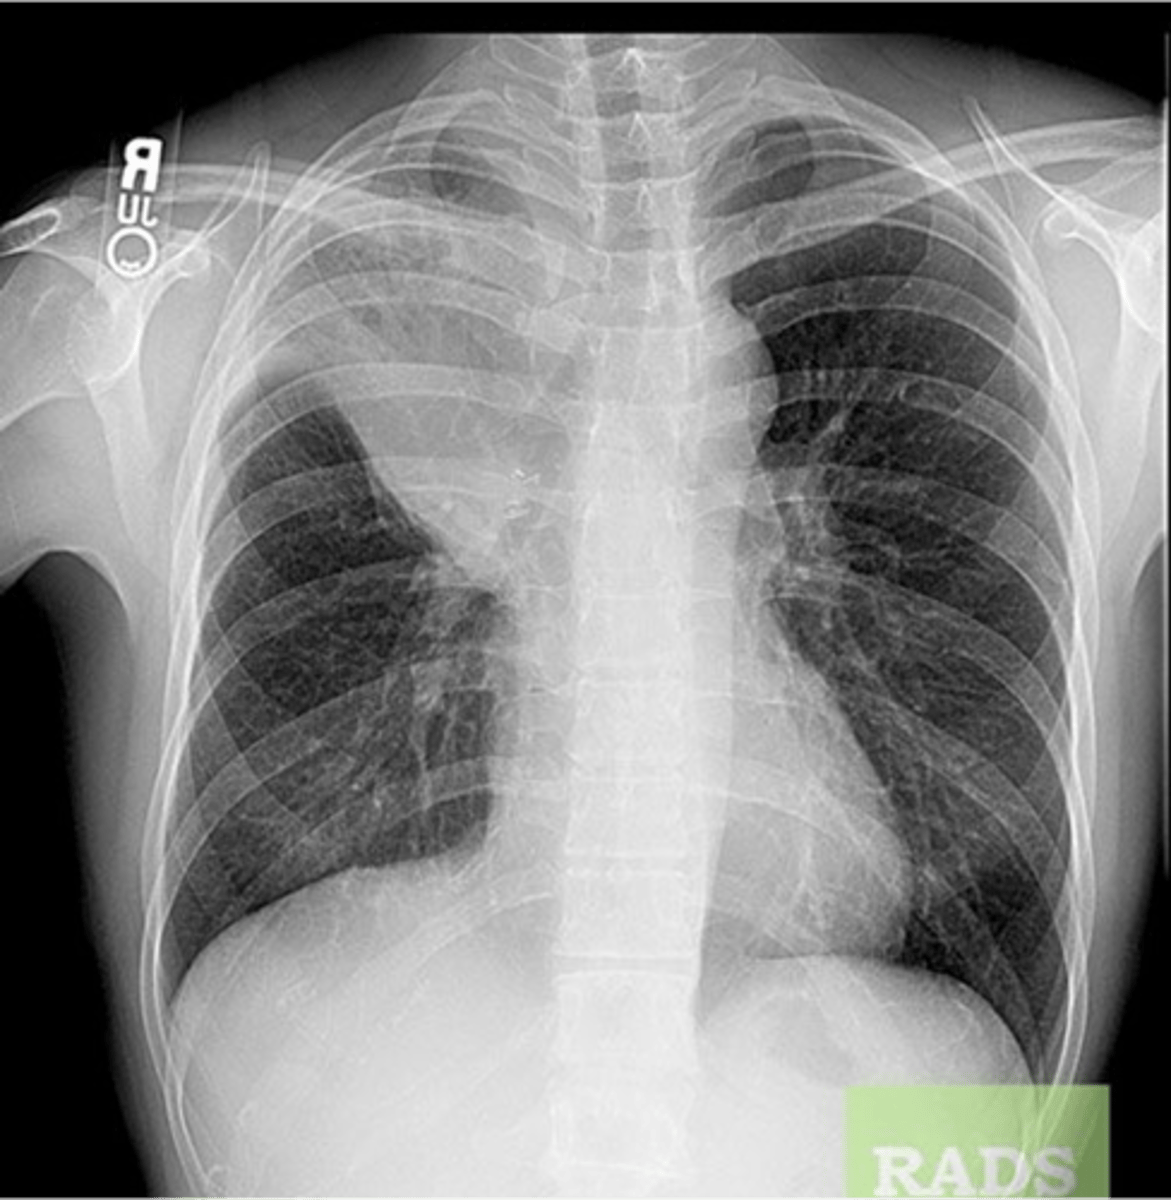

congestive heart failure

congestive heart failure

CHF - severe alveolar infiltrate